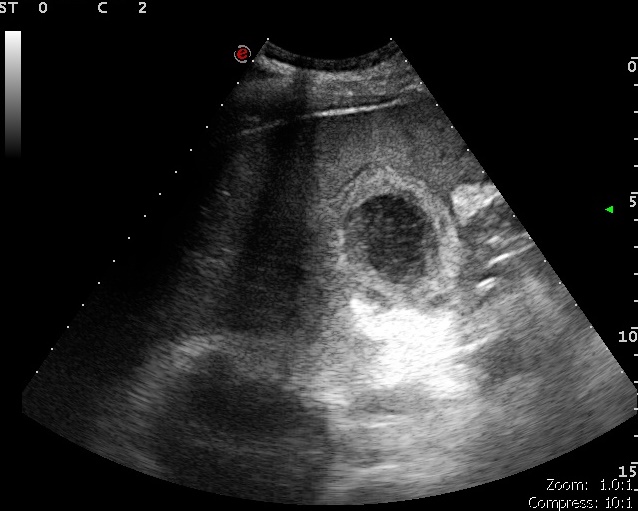

Cholecystitis calculosa Szerző: admin | okt 11, 2010 | Cholecystitis | Nincsenek hozzászólások L.Z. találata Megvastagodott, réteges szerkezetű epehólyagfal. Sűrű epetartalom, kövek. Következményes peritonitisre utaló híg tartalommal telt, peristalticát nem mutató vékonybélkacsok látszódtak a kismedencében 5×190792